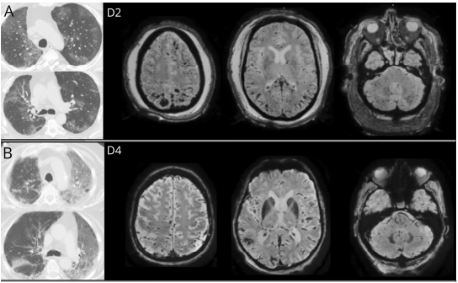

第三项研究由比利时布鲁塞尔自由大学Xavier DeTiège团队主导同期发表在《神经病学》(Neurology)杂志上 。 该研究主要观察重度COVID-19患者的脑部病变和MRI表现 , 鉴于患者具有不稳定性 , DeTiège团队决定瞄准死于COVID-19的患者 。 该团队研究人员对在死后24小时内对患者脑部进行MRI扫描 。 结果显示在4个人中检测到脑实质结构异常 , 包括白质改变、可逆性后脑病变综合征和脑出血 。 研究人员认为 , 这些变化可能是由血脑屏障破坏引起的 , 但并不能说明SARS-CoV-2直接感染脑细胞 。 同时 , 研究还发现了4名患者存在嗅球不对称的情况 。 然而 , 该研究并没有发现明显的脑干变化 , 因此对大脑参与COVID-19呼吸窘迫的说法进行了质疑 。

本文图片

COVID-19患者死后脑MRI成像